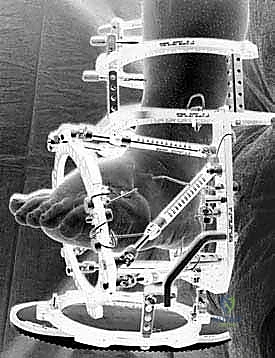

لتجاوز كل العيوب القاتلة للجراحات التقليدية، يبرز تفوق طريقة التصحيح التدريجي على مرحلتين التي يتقنها ويطبقها الأستاذ الدكتور محمد هطيف ببراعة منقطعة النظير. هذه الطريقة تعتمد على مبادئ الميكانيكا الحيوية المتقدمة (استخدام جهاز إليزاروف أو إطارات تايلور المكانية السداسية الأبعاد - Taylor Spatial Frame).

تسمح هذه التقنية بإعادة محاذاة دقيقة ومتحكم بها (مليمتر بمليمتر) للمفاصل المخلوعة أو المتفككة في قدم شاركو. من خلال التشتيت التدريجي (Gradual Distraction)، يتم شد الأنسجة الرخوة والأوعية الدموية والأعصاب ببطء شديد، مما يمنحها الوقت للتكيف والنمو دون أن تنقطع أو تتلف.

هذا النهج يقلل من صدمة الأنسجة الرخوة إلى الحد الأدنى (Minimally Invasive)، ويقلل بشكل شبه كامل من خطر حدوث مضاعفات وعائية عصبية حادة. في حالات قدم شاركو غير المستقرة أو التي لم تلتئم بالكامل، يعتبر التشتيت التدريجي باستخدام التثبيت الخارجي هو "المعيار الذهبي" والعلاج المفضل عالمياً.

2. المرحلة الأولى: تطبيق جهاز التثبيت الخارجي (External Fixator Application)

- التدخل المحدود: بدلاً من شق القدم بالكامل، يتم عمل ثقوب صغيرة جداً (بضعة مليمترات) في الجلد.

- إدخال الأسلاك: يتم تمرير أسلاك معدنية رفيعة جداً وقوية (K-wires) ومسامير نصفية (Half-pins) عبر العظام في الساق والقدم بأماكن استراتيجية محددة مسبقاً بدقة لتجنب الأعصاب والأوعية الدموية، وذلك تحت توجيه الأشعة السينية المباشرة (C-arm) في غرفة العمليات.

- تجميع الإطار: يتم توصيل هذه الأسلاك بحلقات خارجية معدنية أو كربونية تحيط بالساق والقدم (إطار إليزاروف). يتم تثبيت هذه الحلقات معاً بواسطة دعامات قابلة للتعديل.